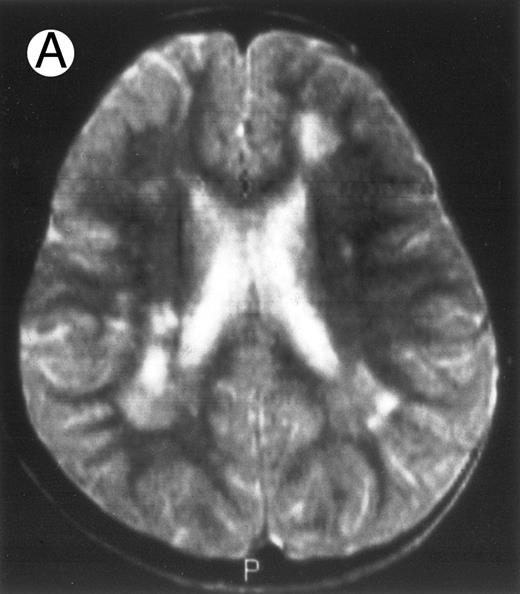

Three different aspects of brain imaging in HLH patients. (A) CT scan of a 3-month-old baby showing a large subdural effusion, several necrotic areas and hypodensities of the white matter. (B) Brain magnetic resonance of a 14-month-old boy showing large confluent areas of hypersignal in T2-weighted images. (C) Large symmetrical necrotic areas of cerebellar white matter in a 41/2-year-old girl (MRI).

Among the nine children with initial neurological symptoms, seizures were the most frequent initial symptom in the youngest patients, whereas ataxia was found in the two oldest patients (46 and 58 months old, respectively) (Table 1). All nine patients had the same CSF abnormalities as patients with meningitis only. Eight of these nine patients had a neuroradiological study performed at the time of their first neurological symptoms (Table 1). The two most frequent lesions were focal necrosis with parenchymal volume loss and atrophy (Fig 2A and C) and white matter abnormalities (Fig 2B). Several small focal lesions with hypersignal at MR imaging that enhanced after administration of gadopentate dimeglumine (or contrast on CT scan) were also observed in two cases.

Abnormalities on brain imaging appeared to roughly parallel the severity of clinical manifestations. All patients with neurological symptoms, but also half of the patients with initial meningitis, had abnormal brain imaging usually consisting of a combination of diffuse white matter abnormalities and necrotic areas with parenchymal volume loss, as previously described.8,23 In patients with isolated meningitis, however, only white matter abnormalities were detected, whereas necrotic lesions and cerebral atrophy were found in patients with neurological symptoms. These lesions progressed despite chemotherapy. Previous neuropathological studies have demonstrated infiltration by monocytes and activated lymphocytes of leptomeninges and brain parenchyma along penetrating vessels.24,25 Infiltration is associated with focal and confluent areas of myelin pallor, as well as neuronal loss, tissue necrosis, and cavitation,24,25 findings that were also demonstrated in the neuropathologic study of five patients in our series. Leukocytes infiltrating the CNS probably secrete cytokines and other neurotoxic factors, such as tumor necrosis factor-α (TNF-α), which may be responsible for the myelinic alteration observed in neurologically asymptomatic patients. Infiltrating leukocytes could also activate in parallel the numerous resident brain macrophages (the microglial cells) and astrocytes, which in turn, can secrete neurotoxic glutamate and free radicals.26